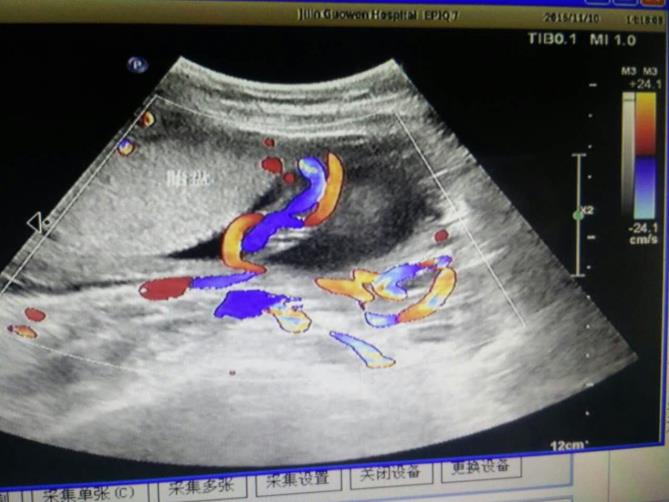

為該患常規(guī)檢查臍帶入口時(shí)發(fā)現(xiàn)臍帶入口位于胎盤下緣邊緣,胎兒超聲檢查無陽性發(fā)現(xiàn)。常規(guī)掃查右卵巢時(shí),發(fā)現(xiàn)右卵巢旁可見腎臟回聲(正常情況下,右卵巢旁是不會(huì)掃查到腎臟回聲的),大小、形態(tài)如常,CDFI:腎內(nèi)血流灌注尚可,故囑患者左側(cè)臥位,顯示孕婦右腎位置、大小及形態(tài)正常,囑孕婦右側(cè)臥位,發(fā)現(xiàn)脾臟下方無腎臟回聲,故考慮該患左腎游走腎。該患于2016年12月2日復(fù)查,結(jié)果如前。